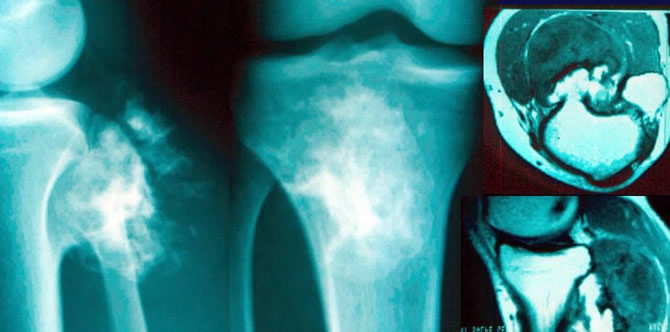

Dégénérescence d'une exostose fémorale

Malade de 42 ans, exostose ancienne peu symptomatique jusqu'il y a 2 mois.

Depuis douleurs et tuméfaction croissante.

Exérèse large d'emblée confirmant la dégénérescence.

Dégénérescence d'une exostose tibiale

Malade de 26 ans ayant remarqué depuis 4 mois une tuméfaction peu douloureuse progressivement croissante du genou.